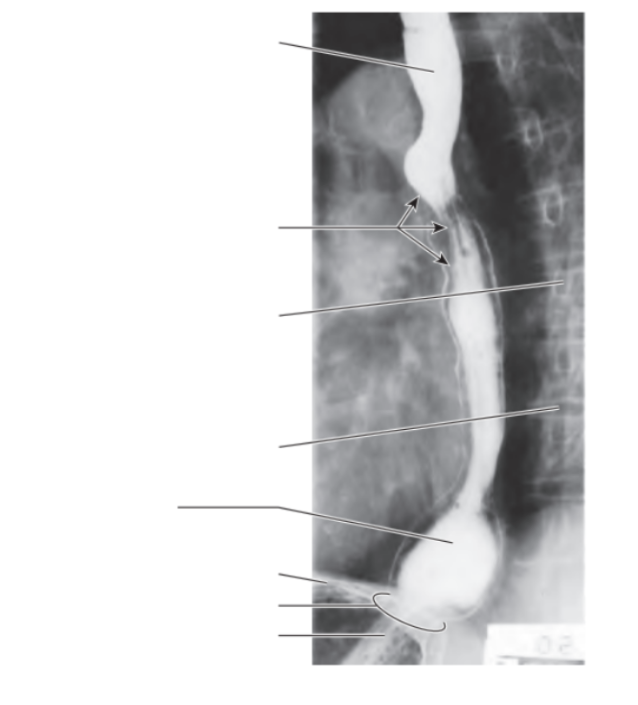

Which part of the small intestine has the most plicae circularis and why?

Jejunum, because it does the most absorption

What happens to the plicae circulares when it goes closer towards the caecum?

It flattens off, meaning it becomes more of a smoother tube

What is the function of plicae circularis

Increase surface area for nutrient absorption

How to differentiate the small intestine from the large intestine

Small intestine has plicae circularis, large intestine doesn’t

Small intestine has lots of villi, large intestine lacks it